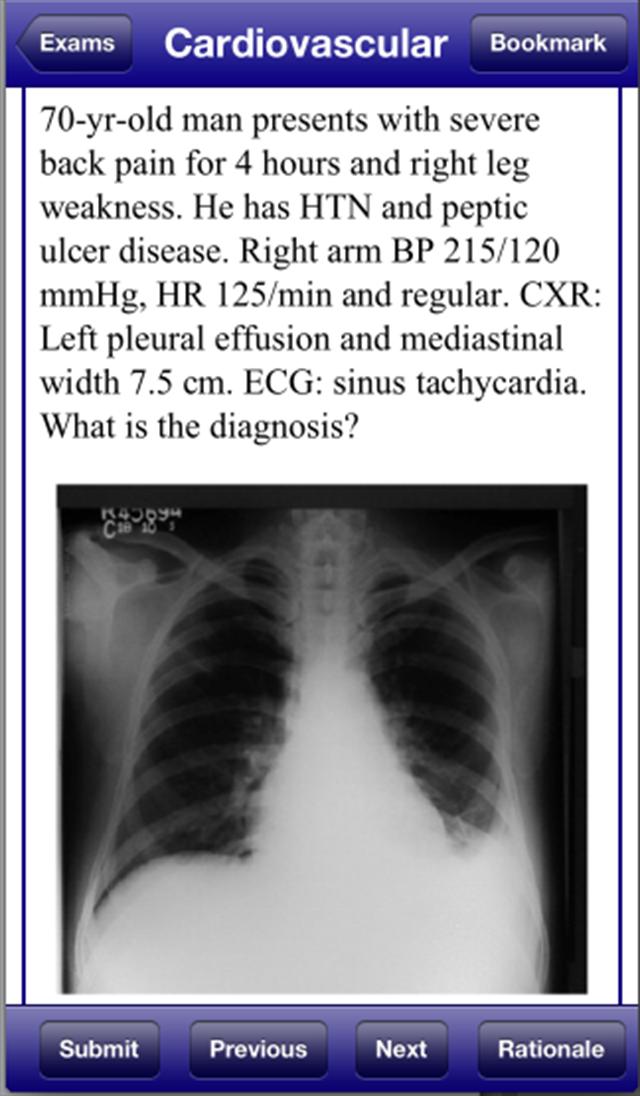

USMLE 2 Stanford Review Course 、David Nobel、MDは、実際のUSMLEステップ2臨床知識検査を再現します。 USMLE 2 Stanford Review Course最新のUSMLE 2試験をレビューした信頼できる医学部教授が書いた1800の質問と回答が含まれています。 USMLE 2 Stanford Review Courseは、CTスキャン、MRI、ECG、皮膚科の写真など、300の画像形式の質問も含まれています。